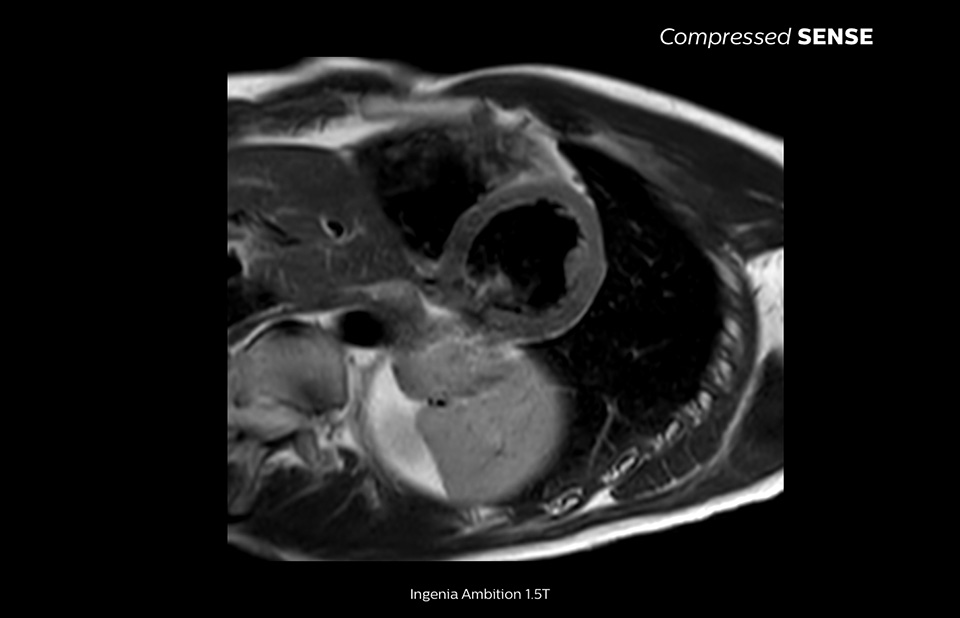

Up to 40% reduction in breathholds, with virtually equal image quality1

Philips Compressed SENSE reduces the time spent in the MRI scanner for the patient. Furthermore, Compressed SENSE enables the reduction of breath hold times which has the potential to improve compliance with an MRI scan.

4.8 sec breath hold time

Since short breath hold times make it easier for our patients to comply, the failure of breath holding largely disappeared.

At our facility, we found in Cardiac MR fewer breath holds are now needed, or breath hold times are shortened."

Dr. Takashi Koyama, MD, PhD, Diagnostic Radiologist and Director of the Department of Radiology Center and Diagnostic Radiology, Kurashiki Central Hospital, Japan

A 15- or 16-second breath-hold is tough for many cardiac patients. With Compressed SENSE we actually have protocols now that can get that below 10 seconds. It’s a lot easier to get through for a patient, and patients are a lot more satisfied with the experience.”

Trevor Andrews, Ph.D., MR Physicist, University of Vermont Medical Center, USA